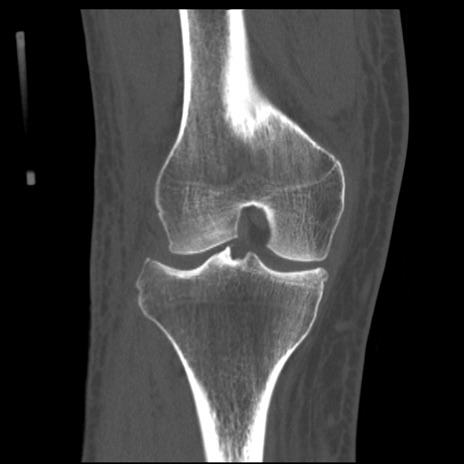

症例28 右膝関節CT(冠状断像)

右膝関節レントゲン

正面像